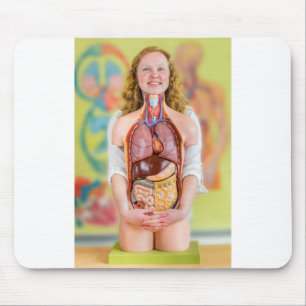

Människatorsoen förkroppsligar modellerar med pussel

Pris256,00 kr

Kroppsmodell hos människa med organ vykort

Pris21,00 kr

Kroppsmodell hos människa med organ anteckningsblock

Pris150,00 kr

Kroppsmodell hos människa med organ vykort

Pris21,00 kr